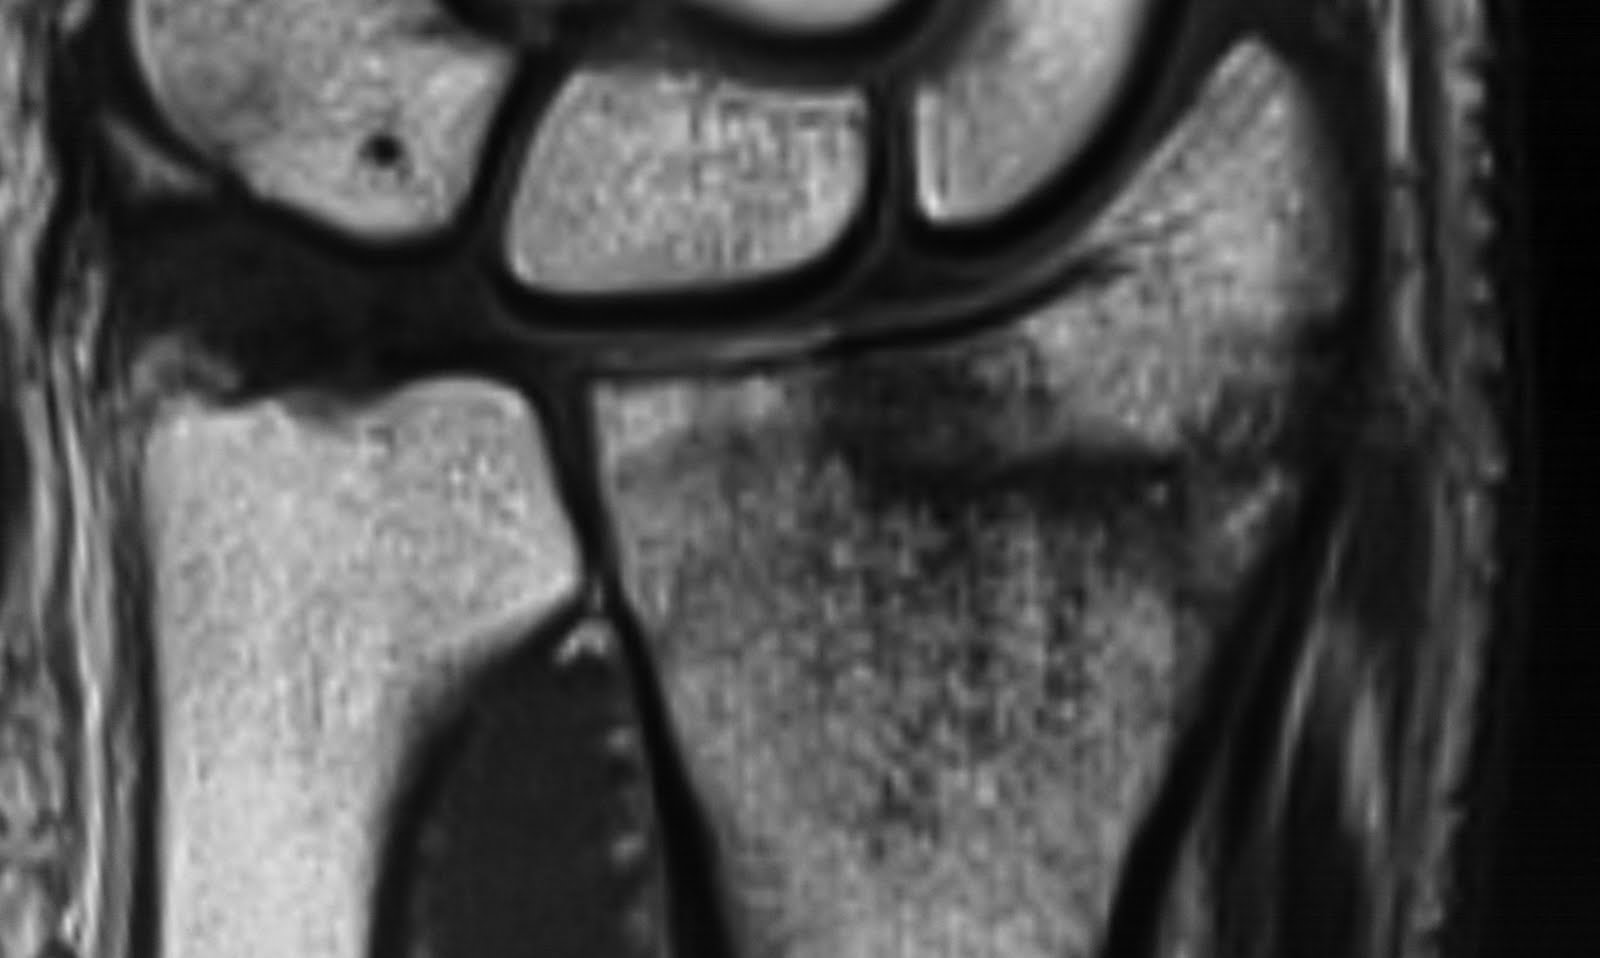

Cpt code ultrasound guided biopsy of thyroid: Management of distal radius fractures. After you find out all wrist scaphoid fracture cpt code results you wish, you will have many options to find the best saving by clicking to the button get link coupon or more offers of the store on the right to see all the related coupon, promote & discount code. It's up to the medical coder whether they wish to use these tracking codes or not. Closed treatment of pelvic ring fracture, dislocation, diastasis or subluxation; The anatomic snuffbox is generally tender and swelling may occur. With fixation of posterior lip is incorrect because there is no mention or implication of fixation of. Scaphoid is most frequently fractured carpal bone, often occurring after a fall onto an outstretched hand. Anatomic snuffbox tenderness is a highly sensitive test for scaphoid fracture, whereas scaphoid compression pain and tenderness of the scaphoid tubercle tend to be more specific. The coding, billing and reimbursement of any medical treatment or procedure is highly subjective, and is dependent upon the interpretation of multiple variables, to include differing medicare fiscal agent local coverage determinations, and a wide. It is used for study and medical insurance statistics and payment. Physicians must explain the patients that the fee covers not only the material like splint. A scaphoid fracture is usually caused by a fall on to an outstretched hand. Cpt® is a registered trademark of the american medical association (ama). A scaphoid fracture is a break of the scaphoid bone in the wrist. Below are 46 working coupons for scaphoid fracture cpt code from reliable websites that we have updated for users to get maximum savings. If there remains sufficient clinical suspicion.